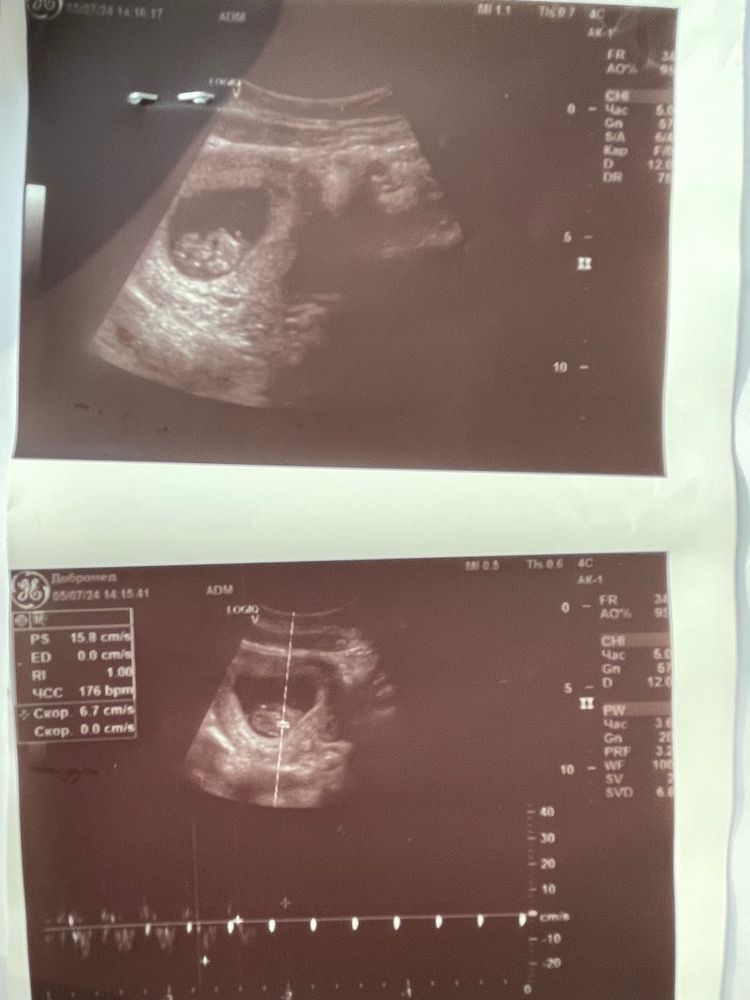

Сходили с мужем на УЗИ в прошлый четверг (4.07, срок был 9+5). Это был Первый раз, когда супруг пошел со мной.

По факту всё хорошо. КТР подрос до 29,3 мм, соответствует сроку. СБ - 176. «Кучка» активно шевелится и растёт ☺️